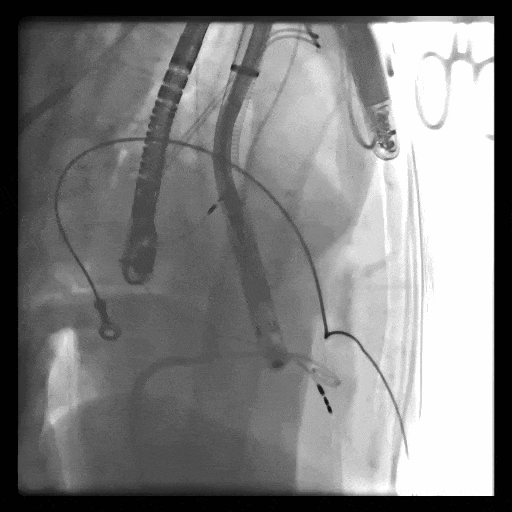

第一例患者手術(shù)難點(diǎn)

1、血管入路問(wèn)題,最窄處平均徑5.5mm(小于8.5mm),輸送器存在進(jìn)入受阻礙風(fēng)險(xiǎn); 2、投照體位過(guò)大,RAO76°,術(shù)中影響輸送器操作可能性大;3、三尖瓣環(huán)大,同軸性難調(diào)整,易產(chǎn)生瓣周漏;4、起搏器導(dǎo)線(xiàn)在三尖瓣瓣環(huán)中心位置穿過(guò),且較短,可能限制人工瓣膜展開(kāi),且尖端靠近室間隔錨定區(qū),可能影響錨定;5、三尖瓣極重度反流,藥物不能緩解患者的癥狀,在應(yīng)用LuX-Valve Plus之前,心臟專(zhuān)家經(jīng)長(zhǎng)時(shí)間評(píng)估均未為患者找到合適的產(chǎn)品或治療方案。

術(shù)中DSA顯示起搏器導(dǎo)線(xiàn)的干擾,右心室造影確定瓣環(huán)位置,操作空間小